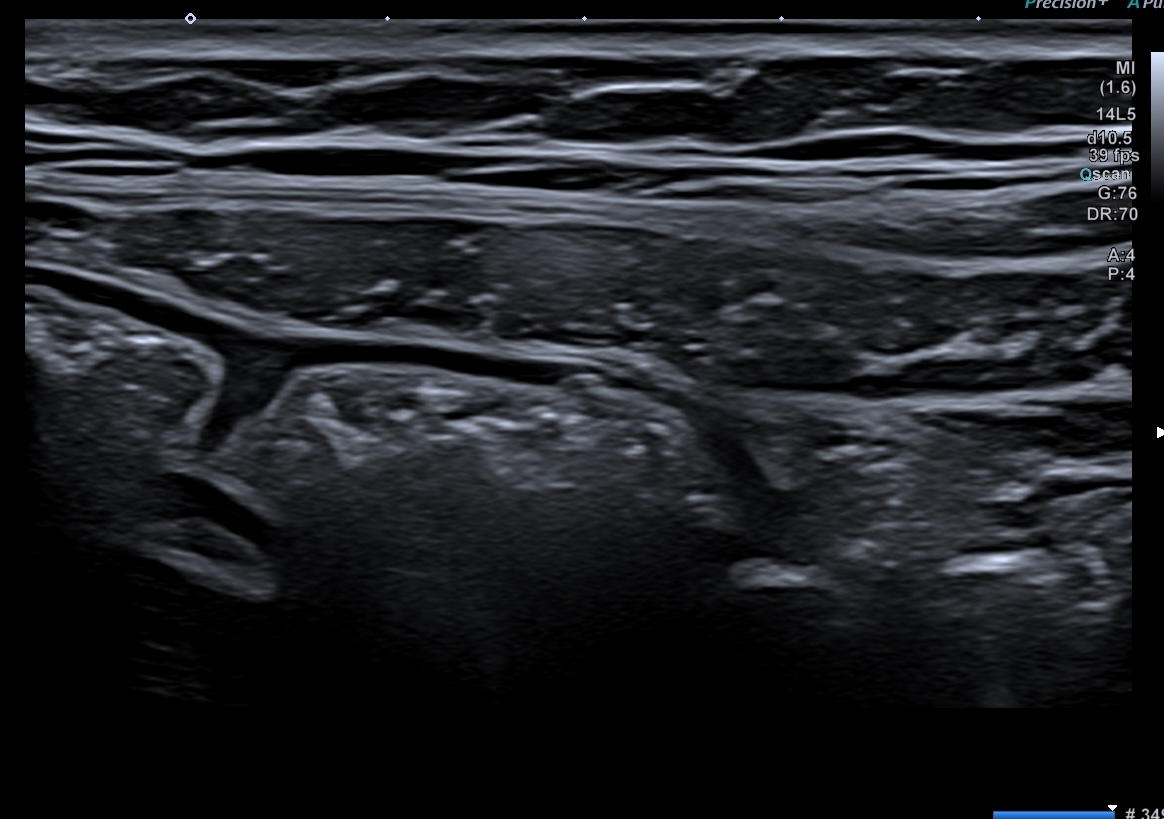

Echographie des cas numéro 2 puis 3

Epaississement entre 4.5 et 7 mm selon les segment, la structure en couche disparait totalement par endroit, à d’autre elle est partiellement conservée. Activité doppler intense de la paroi

Le Score de Milan (MUC) est à (1,4 x7+2) = 11,8

Là encore la paroi est très hypoéchogène, la structure en couches est par endroit totalement absente, ulcérations en surface, infiltration de la graisse, doppler intense, petites adénopathies périphériques.

Le rectum est bien vu avec la sonde basse fréquence la paroi atteint 10 mm à ce niveau.

Le score de Milan MUC est de (10 x1,4+2) = 16